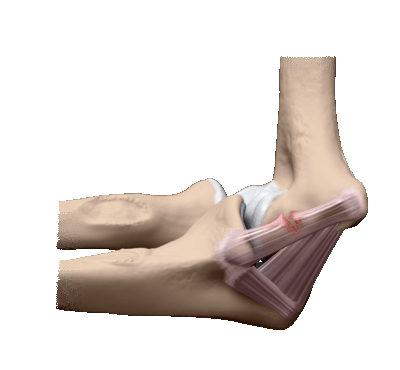

Доступ к головке лучевой кости. Локтевой сустав.

Положение больного - на спине, рука отведена, лежит на боковом столике, согнута в локтевом суставе и пронирована. Кожный разрез начинают со стороны наружного надмыщелка плечевой кости и ведут косо книзу и кнутри. Разрез кожи длиной приблизительно 10 см проводят от локтевого отростка по гребню локтевой кости. Кожу слегка отделяют, рассекают подкожную фасцию и надкостницу по линии кожного разреза. С медиальной стороны открываются косые волокна локтевой мышцы (m. anconeus). С другой стороны расположены волокна локтевого разгибателя запястья и супинатора. Их тоже отделяют субпериостально и отводят кнаружи. Распатор необходимо двигать сверху вниз по локтевой кости. Капсулу рассекают продольно и обнажают головку лучевой кости (рис. 4). При резекции головки лучевой кости следует осторожно обойти подъемником вокруг шейки лучевой кости и на этом уровне долотом произвести резекцию (рис. 5). Супинатор вместе с глубокой ветвью лучевого нерва остается вне операционного поля и нерв не травмируется.

4. Линия разреза при заднем доступе к головке лучевой кости.

5. Задний доступ к головке лучевой кости и верхней трети локтевой кости.